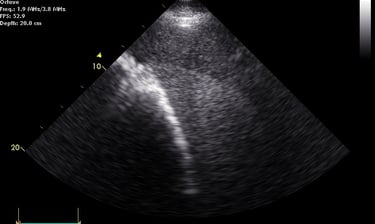

Heeft uw paard een hartruis? Dan is het aanbevolen om een echocardiografie (hartonderzoek) en een inspanningstest met elektrocardiogram (EKG) te laten uitvoeren. Zo kunnen we beoordelen of het veilig is om uw paard te berijden. Een hartruis is namelijk niet altijd een probleem. Met een echocardiografie onderzoeken we of het hart een normale structuur en werking heeft en bepalen we de ernst van eventuele klepafwijkingen.

Voor een uitgebreid hartonderzoek hoeft u niet langer naar een kliniek. Zowel de echocardiografie als de inspanningstest met elektrocardiogram kunnen eenvoudig bij u ter plaatse worden uitgevoerd.

Hartonderzoek - Echocardiografie - Electrocardiografie (EKG)